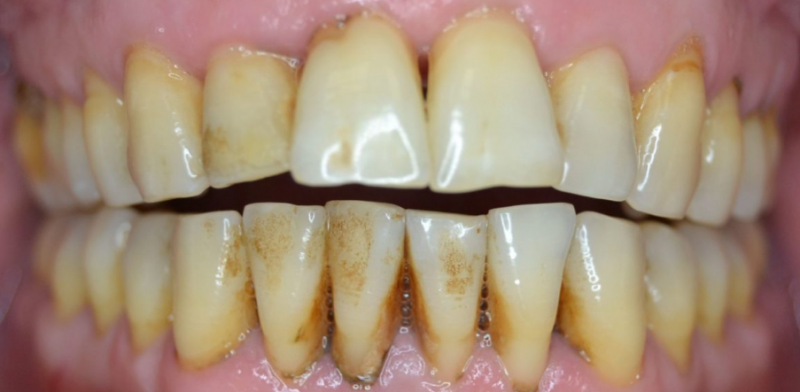

Профессиональная гигиена особенно важна при ортодонтическом лечении, ведь в повседневной жизни, дома, очень сложно поддерживать должный уровень гигиены полости рта! Даже если вы используете ирригатор и специальные ёршики! В нашей рубрике «до/после» вы видите то, что может быть с зубами при лечении брекетами, если не проводить своевременную чистку у врача-стоматолога. Марухно Дарья Александровна провела профессиональную чистку в несколько этапов, чтобы вернуть пациентке белизну ее собственных зубов! Брекет-система была поставлена не в нашей клинике, и почему пациентка не обратилась за профессиональной помощью раньше-вопрос) Но в данном случае, главное – итог! Кровоточивость после даже обычной чистки в такой клинической ситуации – естественный результат. Ведь обильный зубной налёт и зубной камень вызывают воспаление дёсен в виде гингивита, а порой даже пародонтита.

Доктор: Марухно Дарья Александровна